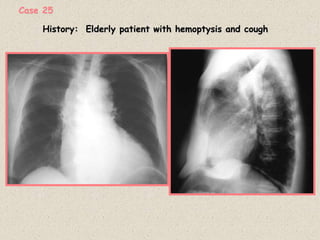

History: Elderly patient with hemoptysis and cough

Case 25

A CT scan of the chest is shown

RUL bronchus

Diagnosis: Right Upper lobe collapse due to an

endobronchial carcinioma